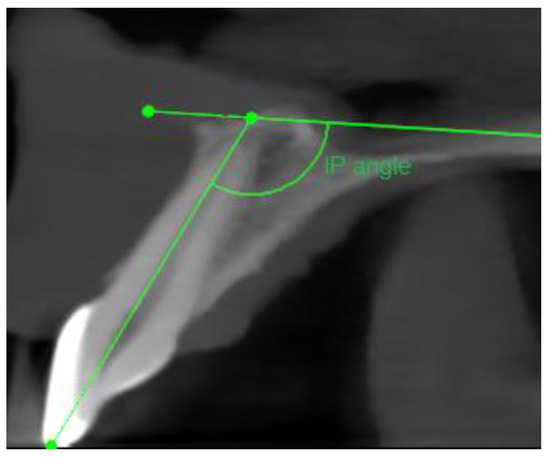

- Sagittal plane:

- Angle formed by the long axis of the incisive canal and the palatine plane—IP angle.